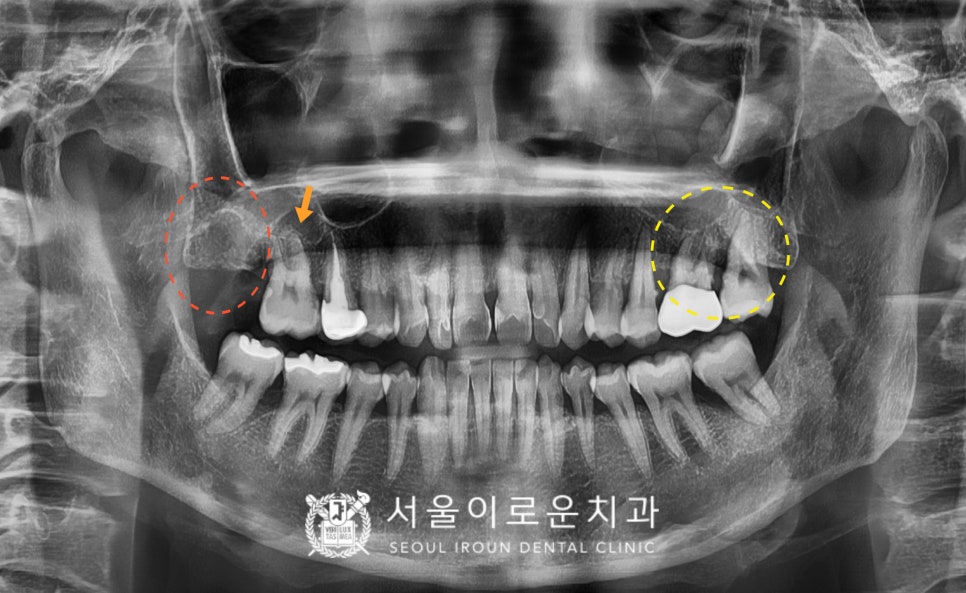

정밀한 검사를 위해

파노라마 사진을 촬영해 보았더니,

✅ 노란색 동그라미 표시의

위턱 왼쪽 큰 어금니 두 개(#26,27)는

심한 치주염으로 인해

2도 동요도를 보이고 있었는데요.

치아 뿌리를 잡고 있는 잇몸뼈가

염증으로 인해 흡수가 많이 되어 있어

살려 쓰기 힘들 것이라 판단되어

안타깝게도 발치 후

임플란트를 계획했습니다.

✅ 빨간색 동그라미 표시의

위턱 오른쪽 두 번째 큰 어금니(#17)는

발치하신지 상당 기간 지났으며,

잇몸뼈에서 상악동까지의

수직적 거리가 충분하여

별도의 뼈이식 없이

임플란트 식립을 계획하였습니다.

✅ 주황색 화살표 표시의

위턱 오른쪽 첫 번째 큰 어금니(#16)는

치아 사이 부분에 충치가 보였는데요.

이 충치로 인해 환.자분께서 평소

저작 시 날카로운 통.증을 보이셨습니다.

우선 충치 부위만 제거한 뒤

본을 떠서 부착시키는

인레이 치료로 계획하였는데요.

충치 제거 후 치료 계획이 변경될 수 있음을

미리 환.자분께 설명해 드리고

치료를 시작하였습니다!